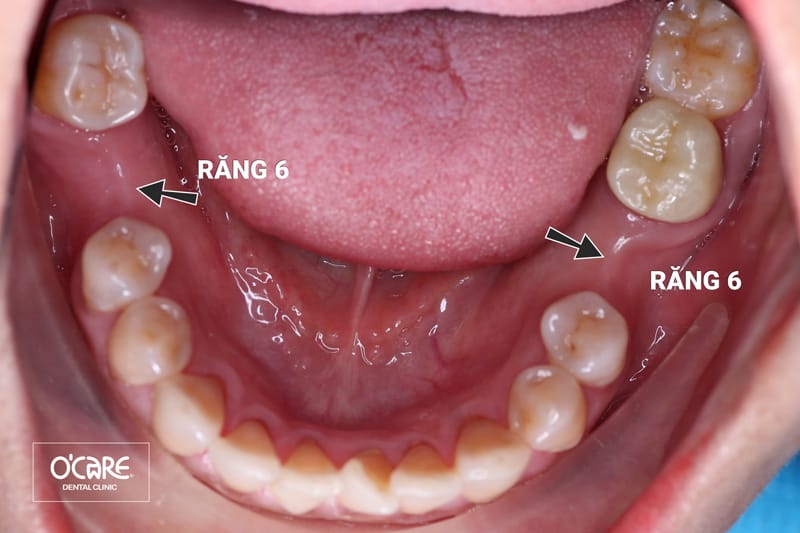

Mất 2 răng số 6 lâu năm

Răng kế cận nghiêng đổ, xô lệch

Răng đối diện trồi xuống

Tác hại mất răng số 6